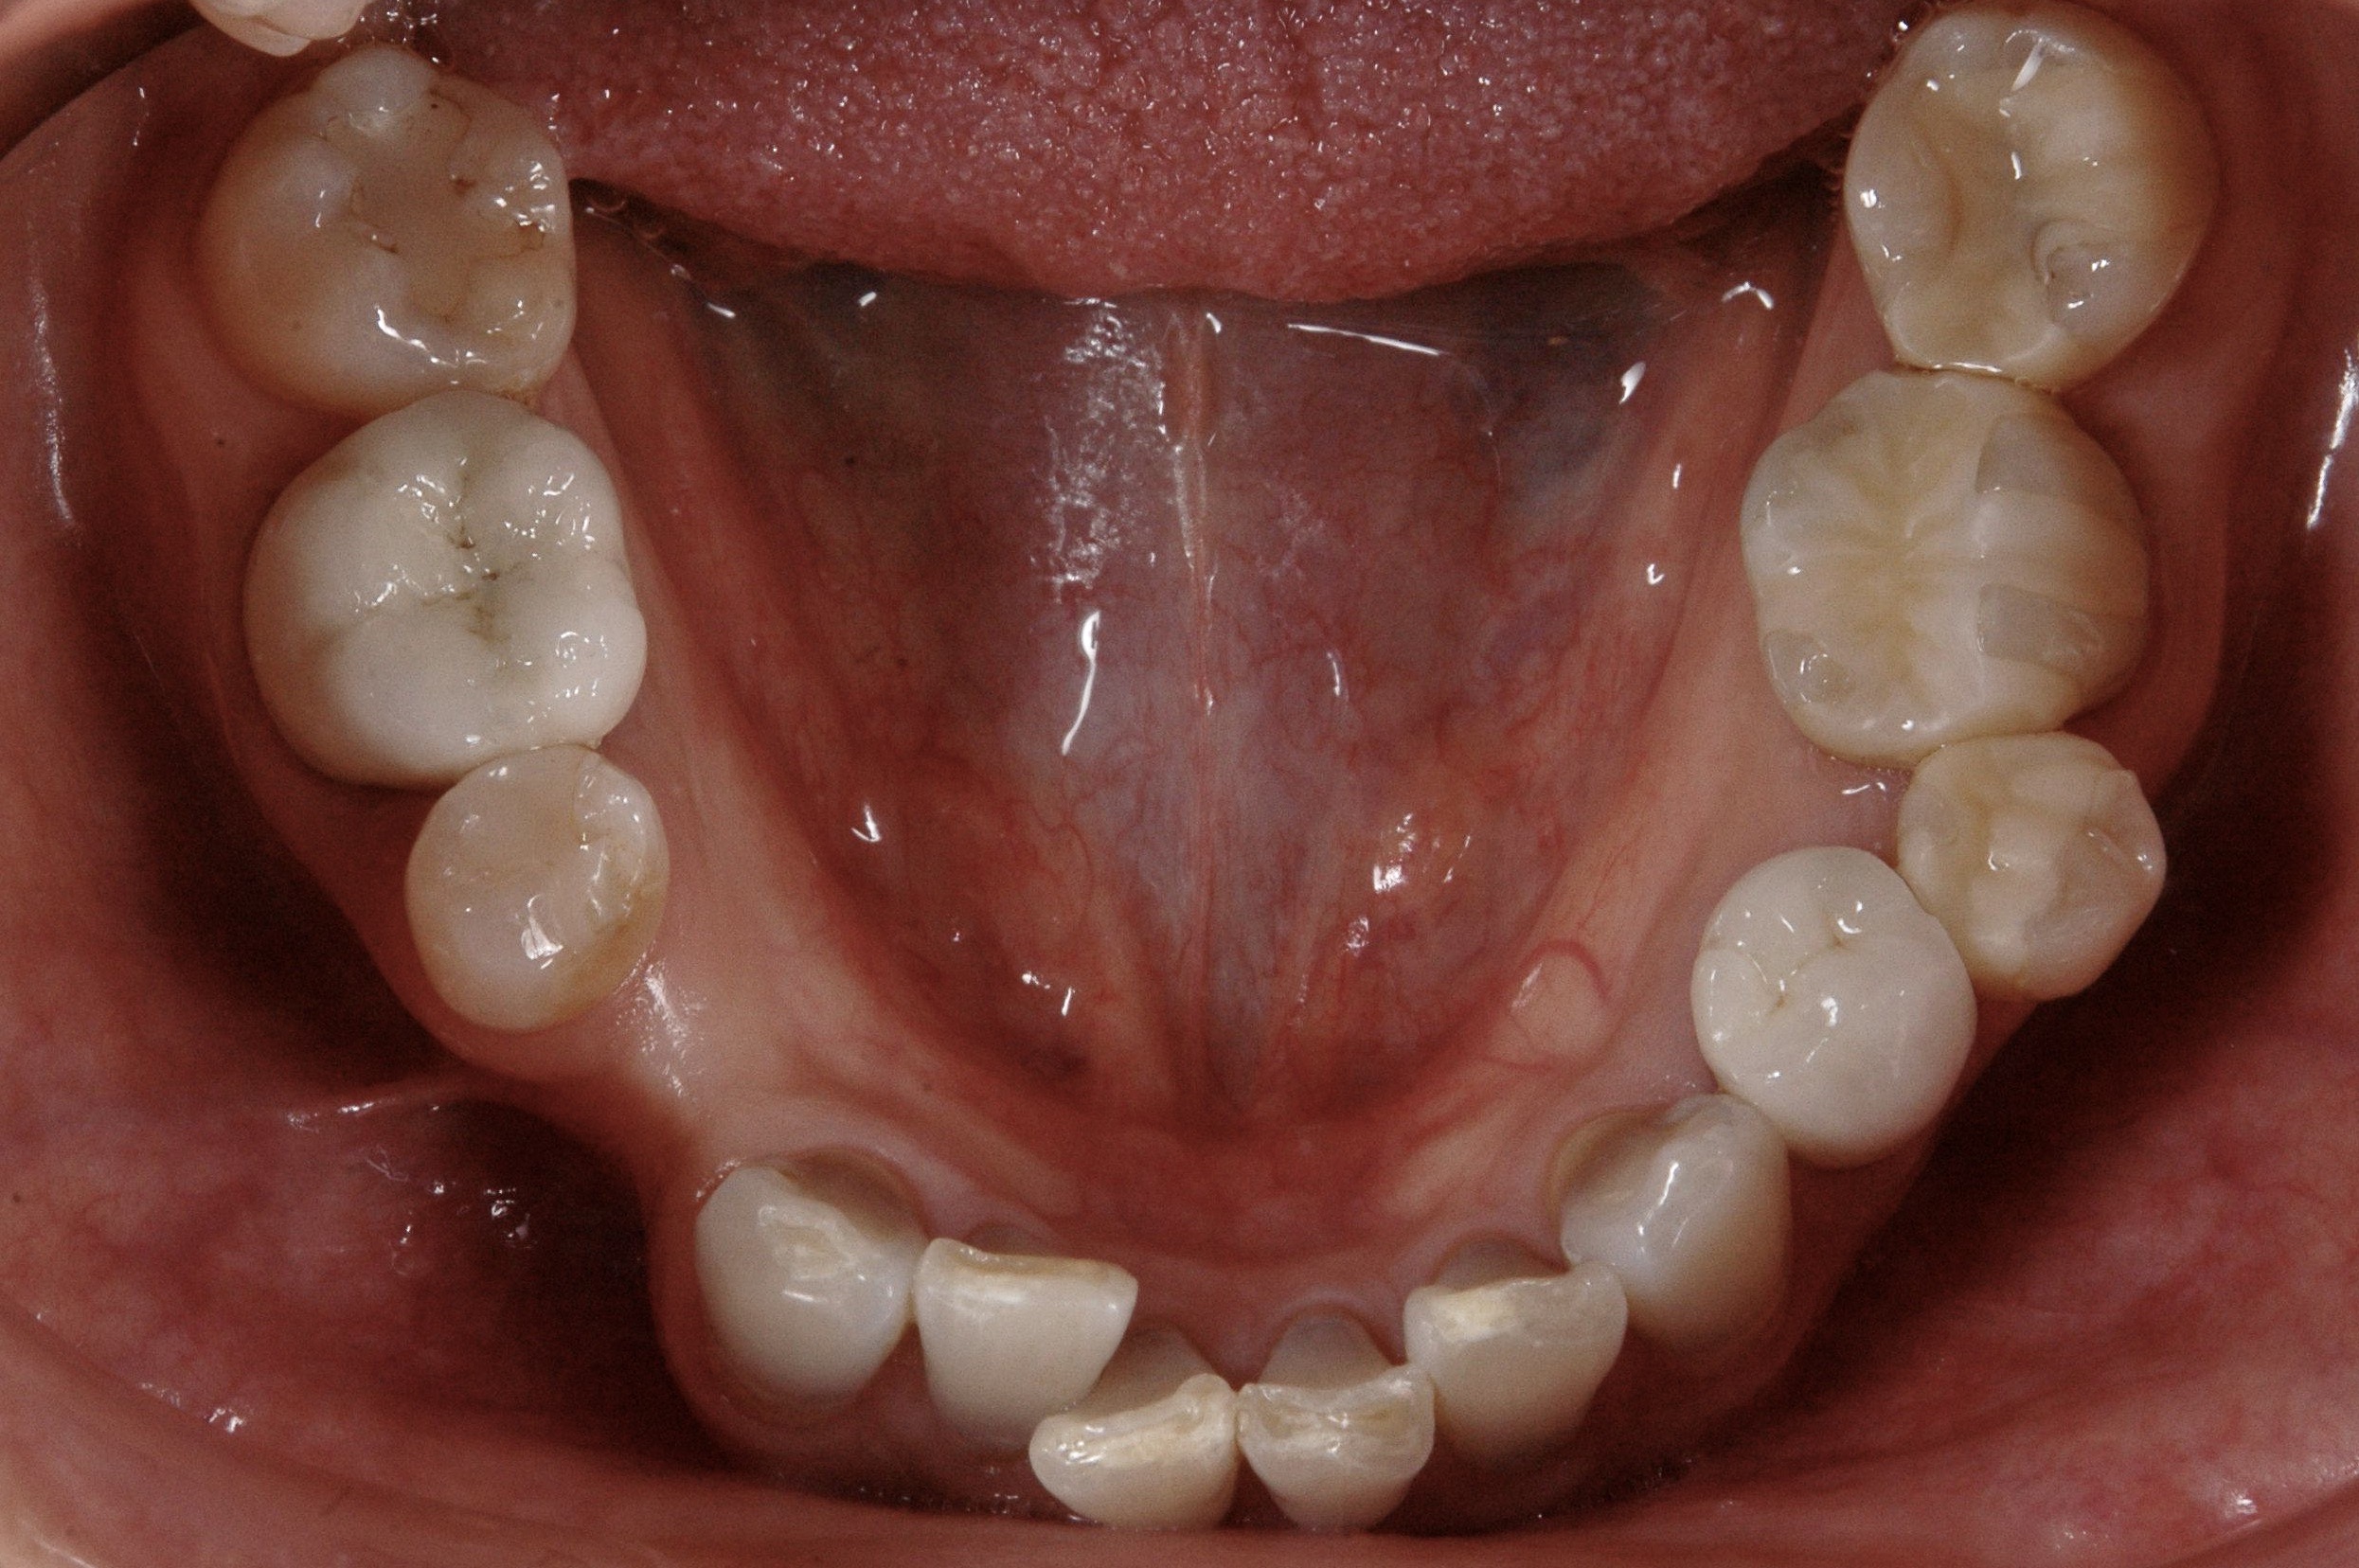

下の歯もすり減りや歪みが目立ち、小臼歯も1本欠損しています。。。